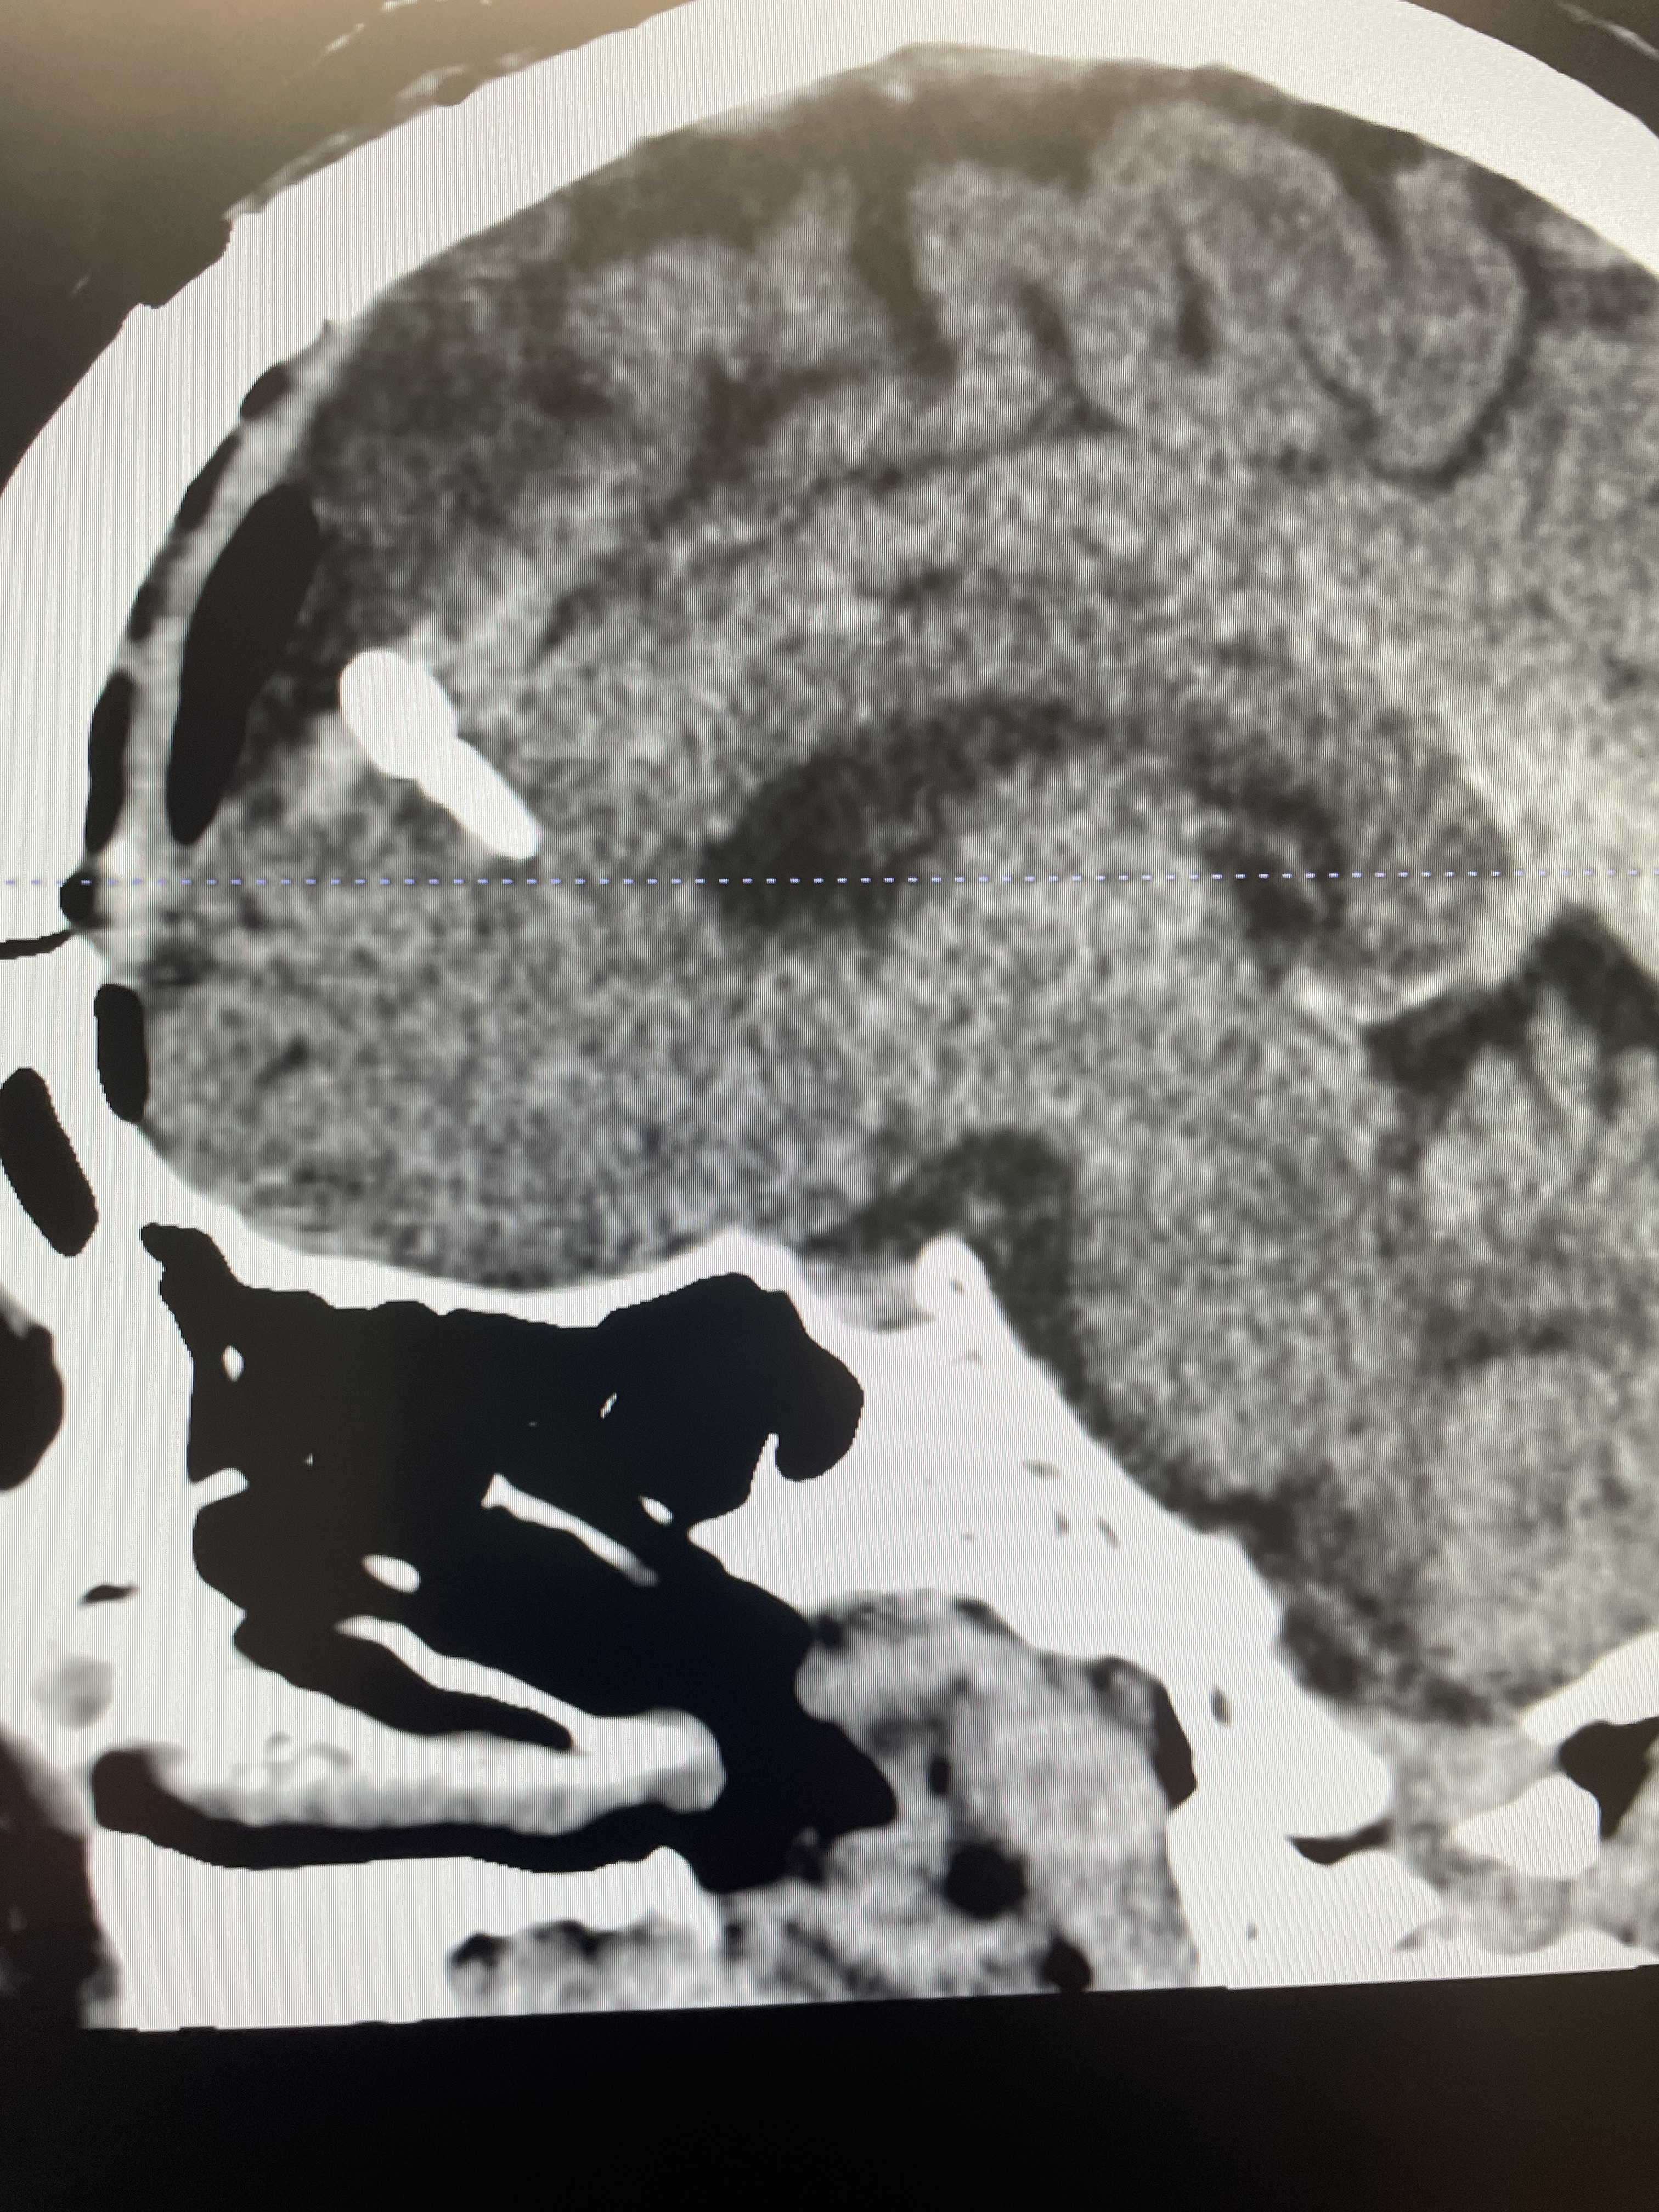

Well, I got my stitches out today. I thought they were going to be bigger. Didn’t hurt, just had a little. I asked him for FMLA for a few weeks just to rattle my brain. I’m gonna try and work a couple of days a week, and just kind of move myself back into full-time. I’m still very tired and I get headaches. Overall, I’m not doing too badly but I definitely am still feeling like I’ve been whacked upside my head.